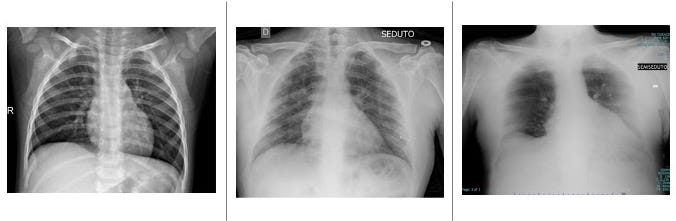

Content Dataset Is Organized Into 2 Folders (Train, Test) And Both Train And Test Contain 3 Subfolders (Covid19, Pneumonia, Normal).

To generate the covidx dataset, we combined and modified five different publicly available data repositories: Users solve the problems by running their solutions on their computer, processing the given dataset, and copy/pasting the output to check the answer. In 2019, fitbit was the fifth largest.